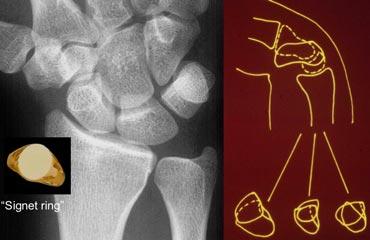

TRÁI: X-quang cổ tay tư thế thẳng sau-trước ở tư thế lệch quay cho thấy xương thuyền bị ngắn lại: dấu hiệu nhẫn đeo tay. PHẢI: Hình minh họa sơ đồ cổ tay ở tư thế gấp cho thấy xương thuyền nghiêng về phía lòng bàn tay

Cả khi lệch quay lẫn khi gấp cổ tay, khoảng trống giữa mỏm trâm quay và xương thang đều bị thu hẹp. Do xương thuyền lấp đầy khoảng trống này, nó sẽ bị ngắn lại và nghiêng về phía lòng bàn tay. Điều này tạo ra hình ảnh xương thuyền có dạng nhẫn đeo tay (hình minh họa).